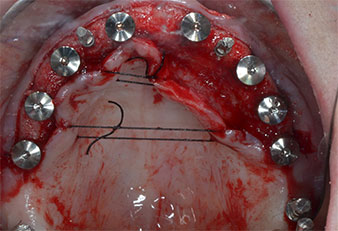

Tre anni dopo era il momento di una protesi dentaria mascellare dello stesso tipo. In base alla pianificazione con CBCT, il rialzo del seno mascellare è stato evitato con l'ausilio di impianti corti e una dima chirurgica è stata utilizzata per trasferire le posizioni pianificate alla cresta alveolare (Figg. 1 e 2).

Fig. 2: dopo l'incisione crestale sulla linea mediana e la preparazione dei lembi mucoperiostei, le posizioni dell'impianto vengono trasferite all'osso.

A causa dell'osso relativamente duro (D2) in quest'area, le sedi dell'impianto di 10 mm nelle posizioni 11 e 21 sono state finalizzate con un trapano rotante da 4 mm di diametro, in combinazione con un contrangolo chirurgico W&H WS-75 L, il motore per impianto W&H Implantmed e il modulo opzionale Osstell ISQ di W&H. Al contrario, a causa dell'osso morbido, le sedi posteriori sono state preparate a un diametro finale di 3 mm utilizzando lo strumento Piezomed I3P. Gli impianti sono stati infine posti per via transgengivale sull'osteointegrato per tre mesi (Figg. 6-10). La protesi dentaria esistente è stata mantenuta su quattro impianti provvisori (Fig. 8).

Impianto a livello tissutale da 10 mm

Fig. 6: un impianto a livello tissutale da 10 mm è posto in posizione 21. L'impianto in posizione 11 e i tre impianti posteriori da 4 mm sono già in posizione.